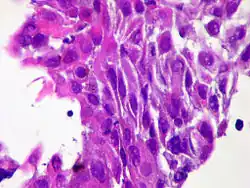

Micrograph of squamous-cell carcinoma (H&E stain)

Squamous epithelial cells are not found in a normal thyroid, so the origin of SCT is not clear. However, it might be derived from embryonic remnants such as thyroglossal ducts or branchial clefts. Often, SCT is diagnosed in one of the thyroid lobes but not in the pyramidal lobe. Another possible way of developing SCT is through the squamous metaplasia of cells. However, that theory is also controversial since Hashimoto's thyroiditis and chronic lymphocytic thyroiditis (neoplasms to be shown squamous metaplasia) are not associated with SCT. Primary STC is usually diagnosed in both lobes of the thyroid gland. The histopathology of STC shows a squamous differentiation of tumor cells.